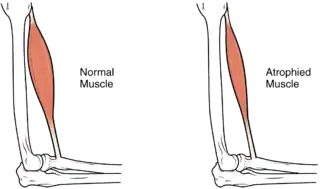

La atrofia muscular es un término médico que se refiere a la disminución del tamaño del músculo, perdiendo fuerza este debido a la relación con su masa.[1] Afecta a las células nerviosas de los músculos esqueléticos, generando parálisis. La parálisis puede ser parcial o completa y generalmente comienza insidiosamente.

El tamaño del músculo se reduce, como consecuencia hay una pérdida de fuerza y movilidad. | ||